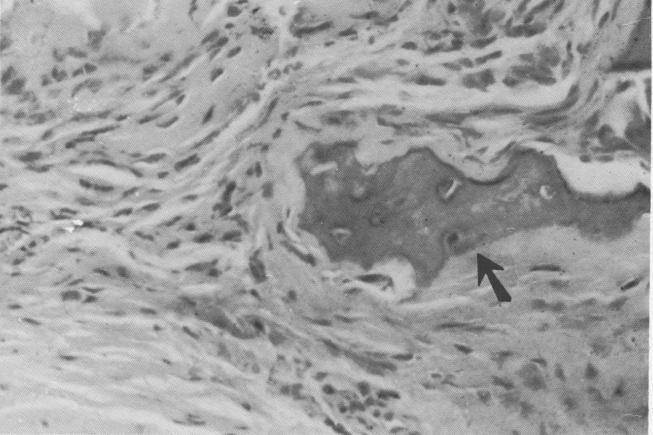

Fig. 4-49. Fibroblasts are evident under higher magnification.

content was less marked than further away from the implant. This is consistent with the variations in cellularity observed in the periodontal membrane.